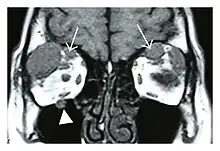

![]() Swelling of the left superior and lateral rectus muscles, a mass lesion around the left optic disc (arrow), and enlargements of the left supraorbital nerve and the right infraorbital nerve (arrow heads) in a 60-year-old man with a serum IgG4 of 463 mg/dL.[1] (T1-weighted MRI) |

![]() Bilateral supraorbital nerve enlargements (arrows) and right infraorbital nerve (arrow head) enlargement in a 47-year-old woman with a serum IgG4 of 1000 mg/dL.[1] (T1-weighted MRI) |